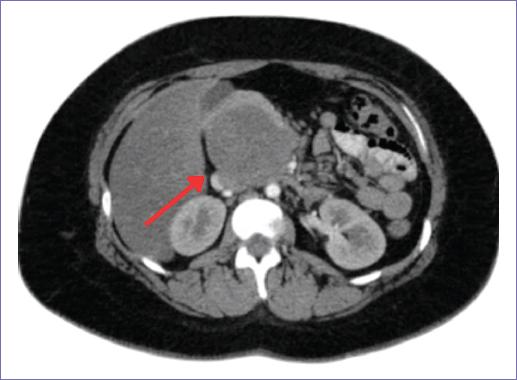

Se trata de una paciente de 20 años, originaria del Estado de México y residente en Pachuca, Hidalgo, sin antecedentes personales patológicos, con antecedentes familiares de diabetes tipo 2, cursando el segundo trimestre de embarazo, quien fue referida al servicio de oncocirugía por la detección incidental de una masa abdominal. En octubre de 2022, la paciente acudió a consulta médica debido a molestias inespecíficas en el abdomen superior, descritas como una sensación de plenitud en el epigastrio. Durante esa evaluación se realizó un ultrasonido abdominal que mostró una masa quística localizada en el epigastrio, con dimensiones de 9.1 x 7.6 x 8.99 cm y un volumen de 324.43 ml, con escasa vascularidad periférica. Ante este hallazgo, se recomendó seguimiento clínico y ultrasonográfico. En febrero de 2023 se realizó un nuevo ultrasonido abdominal como parte del seguimiento. Este estudio reportó una masa quística compleja en el epigastrio con dimensiones de 8.46 x 7.09 x 9.83 cm y un volumen calculado de 306.38 ml, sin cambios significativos en comparación con el estudio previo. A pesar de la estabilidad del tamaño de la lesión, se decidió continuar el seguimiento clínico debido a sus características ecográficas. El embarazo se resolvió sin complicaciones mediante parto vaginal el 21 de abril de 2023. Durante el puerperio, las molestias abdominales disminuyeron; sin embargo persistió la sensación de plenitud en el epigastrio, lo que llevó a la realización de un nuevo ultrasonido el 14 de junio de 2023. En este estudio, la lesión mostró características distintas, siendo descrita ahora como una masa sólida localizada en la cabeza del páncreas, con dimensiones de 6.8 x 7.9 x 7.56 cm y un volumen estimado de 213.79 ml. Además, se reportó hepatomegalia leve, dilatación del colédoco y de la vena porta, lo que indicaba una progresión de la lesión. En agosto de 2023 se realizó una tomografía computarizada simple y contrastada del abdomen para una caracterización más precisa (Fig. 1). Este estudio confirmó la presencia de una masa retroperitoneal de características sólidas y complejas, predominantemente hipodensa en la fase simple, con reforzamiento nodular periférico e irregular en las fases contrastadas, la lesión medía 7.7 x 6.2 x 7.0 cm, comprimía estructuras adyacentes, incluyendo la vena cava inferior y el duodeno, pero no mostraba invasión directa. Ante estos hallazgos, se decidió continuar con análisis de laboratorio, en los que se encontraron biometría hemática normal, función renal y hepática dentro de rangos normales, y marcadores tumorales CA 19-9 y CEA negativos. También se evaluaron catecolaminas en orina de 24 horas, cuyos resultados mostraron niveles normales de adrenalina y noradrenalina, descartando la funcionalidad del tumor. Con base en los hallazgos clínicos y paraclínicos, se plantearon diagnósticos diferenciales que incluyeron pseudoquiste pancreático, tumor sólido pseudopapilar del páncreas y paraganglioma retroperitoneal. Se decidió llevar a cabo un abordaje quirúrgico como tratamiento definitivo. La paciente fue programada para una laparotomía exploradora con resección tumoral en el servicio de oncocirugía. El procedimiento se realizó el 21 de agosto de 2023, bajo anestesia general. Durante la intervención quirúrgica, se identificó una masa de gran tamaño localizada en el retroperitoneo, adherida al duodeno, la cabeza del páncreas y la vena porta. Se realizaron maniobras de Kocher para movilizar el duodeno y permitir un acceso adecuado a la lesión. La resección fue compleja debido a la cercanía de la masa con estructuras vasculares mayores, pero se logró una extirpación completa de la lesión. El procedimiento tuvo una duración de 170 minutos y un sangrado transquirúrgico estimado en 1,500 ml, que requirió la administración de concentrados eritrocitarios. El análisis macroscópico del tejido extraído describió una masa sólida de 9 x 7 x 5 cm, de consistencia firme, coloración café rojiza y bordes bien delimitados (Fig. 2). En el análisis histopatológico se confirmó que se trataba de un paraganglioma retroperitoneal, con un patrón característico de células dispuestas en nidos (patrón Zellballen) rodeados por un estroma fibrovascular. No se evidenciaron atipias celulares, mitosis anormales ni invasión vascular, lo que respaldó su clasificación como una lesión benigna. En el postoperatorio inmediato la paciente presentó estabilidad hemodinámica, aunque desarrolló una fístula pancreática de bajo gasto que fue manejada de manera conservadora con ayuno, soporte nutricional y drenaje percutáneo. La fístula cicatrizó espontáneamente tras cuatro semanas de manejo. El seguimiento clínico y por imagen no mostró evidencia de recurrencia tumoral. Sin embargo, durante las consultas de seguimiento, la paciente presentó hiperglucemia persistente, lo que llevó al diagnóstico de diabetes mellitus tipo 1 secundaria a la resección parcial del páncreas. Fue referida al servicio de endocrinología, donde inició manejo con insulina. Actualmente, la paciente permanece asintomática y sin signos de recurrencia tumoral en los estudios de imagen realizados a los tres y seis meses posteriores a la cirugía. Continúa bajo vigilancia oncológica y metabólica, con un pronóstico favorable.